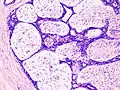

Histopathologic image of breast fibroadenoma. Core needle biopsy. Hematoxylin & eosin stain.

Histopathologic image of breast fibroadenoma showing proliferation of intralobular stroma compressing and distorting the epithelium. H&E stain.

Fibroadenoma of the breast is a benign tumor composed of a biplastic proliferation of both stromal and epithelial components.[12][13] This biplasia can be arranged in two growth patterns: pericanalicular (stromal proliferation around epithelial structures) and intracanalicular (stromal proliferation compressing the epithelial structures into slit-like spaces).

These tumors characteristically display hypovascular stroma compared to malignant neoplasms.[2][14][9] Furthermore, the epithelial proliferation appears in a single terminal ductal unit and describes duct-like spaces surrounded by a fibroblastic stroma. The basement membrane is intact.[15]